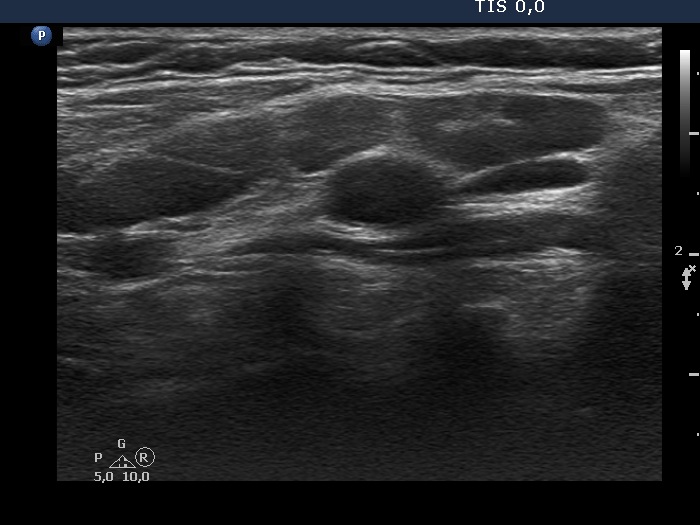

Right lobe, longitudinal scan

Right side of the neck, above the thyroid, longitudinal scan. There are three or four enlarged lymph nodes next to each other.